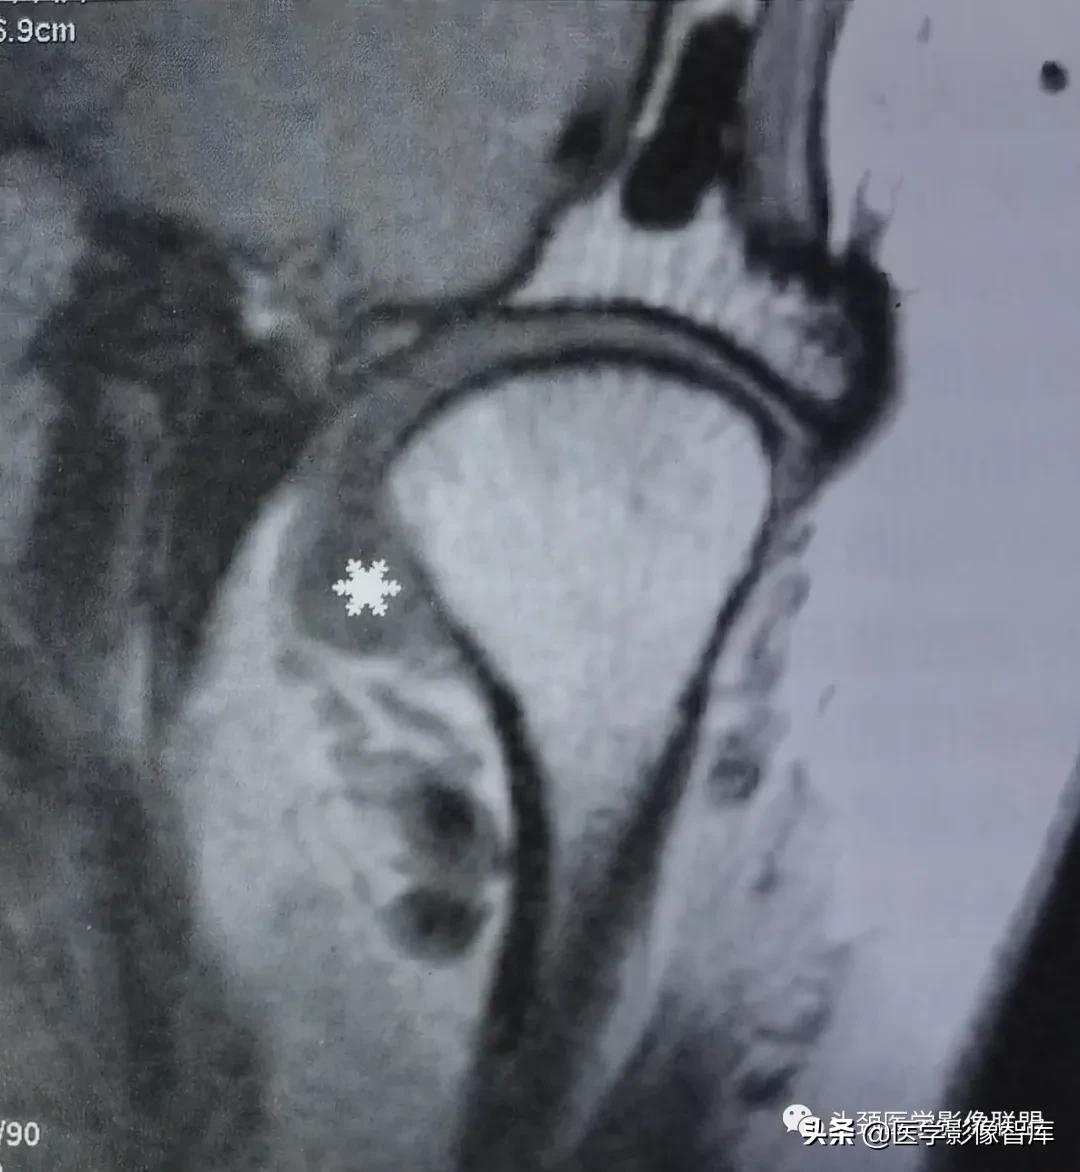

图10-3-8 关节盘后移

矢状面闭口 PDWI示关节盘后带(白星)位于下颌髁突后方。

关节盘后移位是指关节盘的一部分位于下颌髁突之后。盘后移极为罕见。Westesson等统计显示其发生率约为1%。大约50%的关节盘后移伴有关节盘旋转移位。部分患者尚可合并关节盘穿孔。MRI上,如发现关节盘后带位于下颌髁突的后方则可诊断为关节盘后移位 (图8) 。